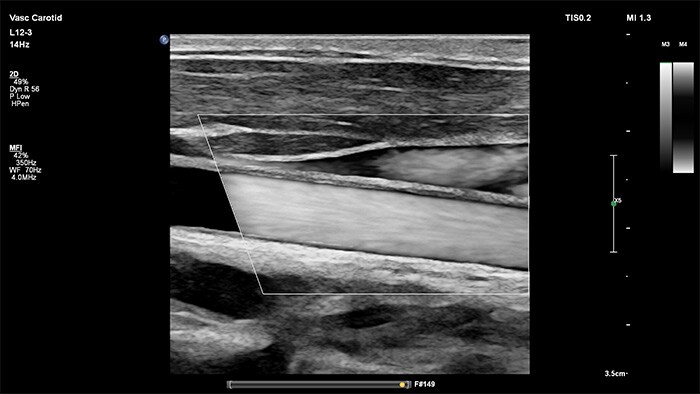

MicroFlow Imaging

MicroFlow Imaging de Philips se ha diseñado para identificar con una extraordinaria sensibilidad las zonas anatómicas que presentan un flujo sanguíneo lento y débil en los tejidos y, además, mejora la resolución del flujo en las exploraciones vasculares. Gracias a su alta resolución y cantidad mínima de artefactos, los profesionales sanitarios pueden visualizar y caracterizar alteraciones sutiles en el flujo alrededor de la placa estenótica para así elaborar diagnósticos fiables.